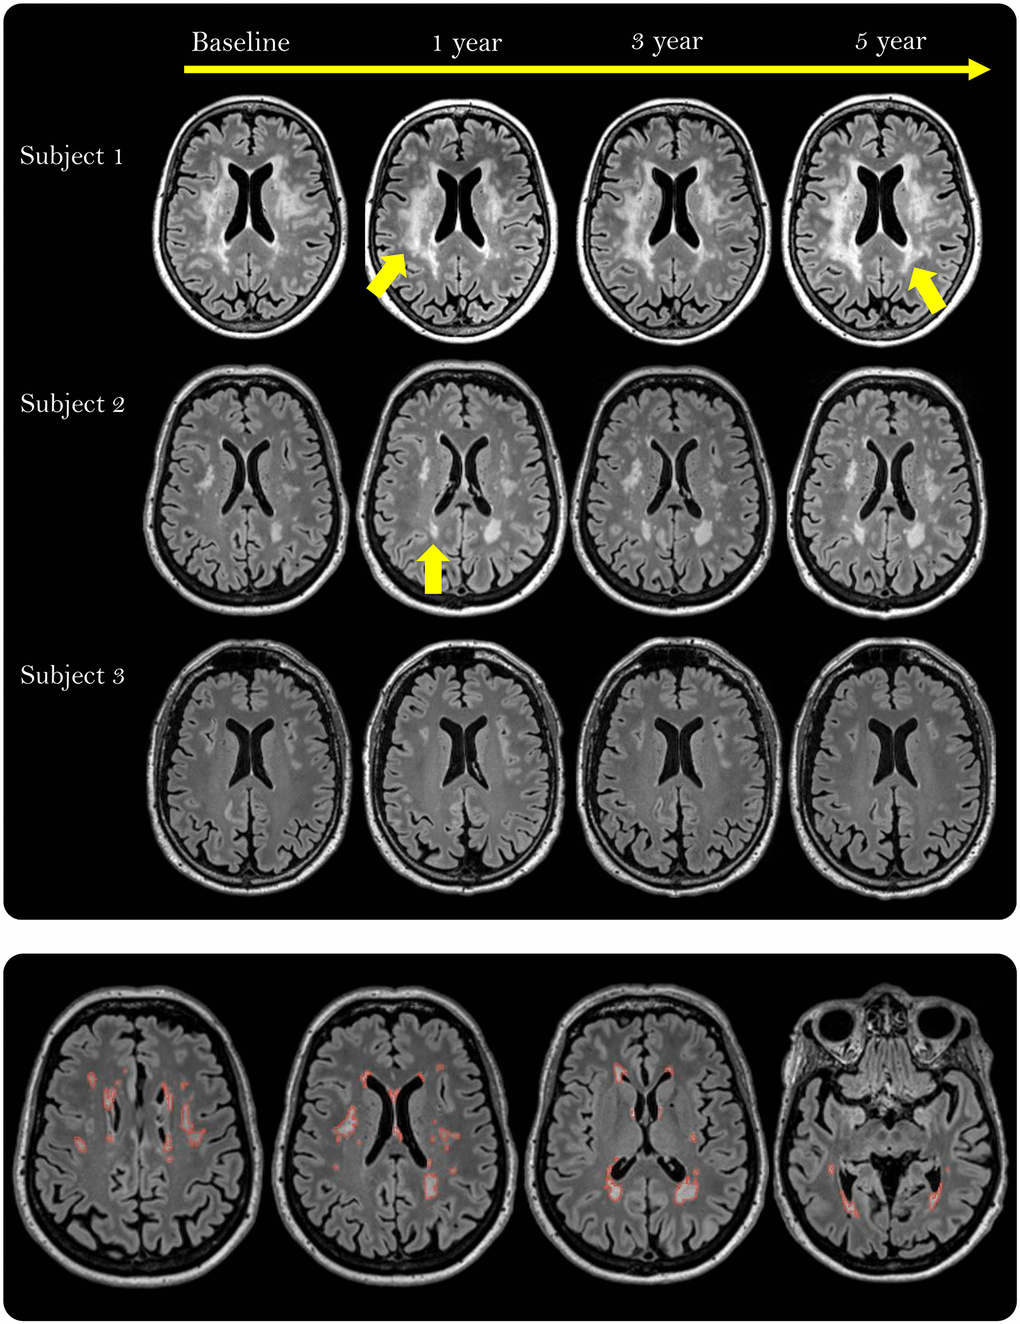

Figure 3. White matter hyperintensities (WMHs) depicted as white, well-defined lesions or confluent areas in white matter on fluid-attenuated inversion recovery (FLAIR) scans in three participants during the 5-year intervention period. The yellow arrows point to areas with growing WMH lesions (Subject 1) or a new lesion (Subject 2). The lower row shows the manually delineated WMHs (red outline) across 4 out of 176 slices in one participant.

To investigate if certain regions of WMH were more sensitive to the effects of the intervention and/or VO2peak, WMH were divided into PWMH and DWMH. Likewise, associations between intervention group and/or VO2peak, and automatically derived WM-hypointensity volume from T1-weighted scans, which are considered to reflect more severely affected WMH regions [44, 83, 84], were assessed.